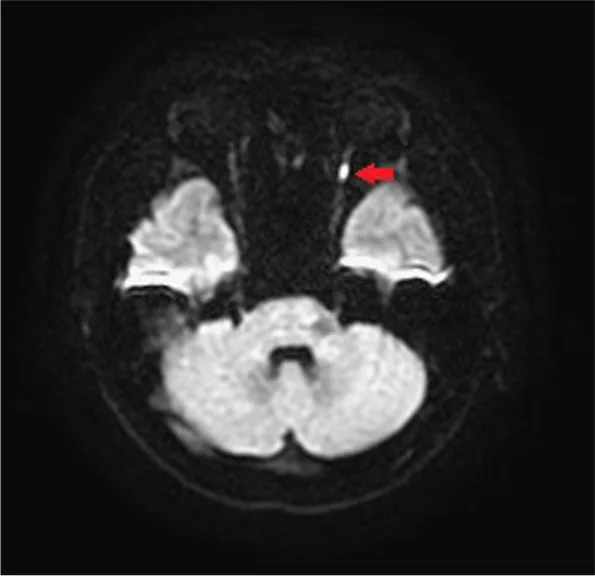

Using diffuse weighted image and apparent diffusion coefficient in MRI for diagnosis of posterior ischemic optic neuropathy in a young male: a case report and literature review. BMC Ophthalmol. 2022 Apr 14; 22:168. Figure 4. PM

CI D: PMC9009014. License: CC BY.

T2WI DWI showed focal high intensity signal at the left optic nerve. (Red arrow)

拡散強調像(DWI) :後部視神経 における拡散制限(ADC低下)が確認できる場合がある。細胞毒性浮腫により水分子が細胞内に蓄積することで拡散制限が生じる。ただし成功例はわずかである。